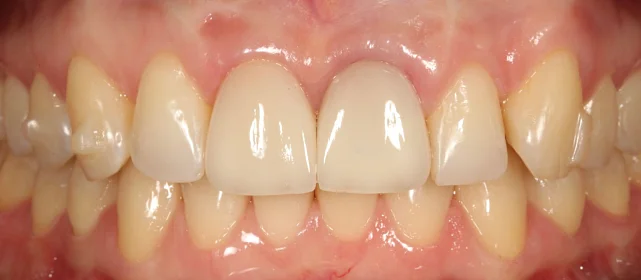

Зубы выровнены, смыкание нормализовано. Установлены несъёмные ретейнеры на обе челюсти, изготовлены ретенционные капы. Пациентка предварительно проконсультирована ортопедом онлайн.

Решение: Поставили элайнеры 3D Smile на обе челюсти. Лечение заняло 4 года и потребовало нескольких последовательных этапов коррекции. Капы менялись каждые 1–2 недели, на контрольных визитах отслеживали прогресс и выдавали новые наборы. Зубы встали в правильное положение, смыкание нормализовалось. Зафиксировали ретейнеры на обе челюсти, изготовили ретенционные капы. Пациентка прошла онлайн-консультацию с ортопедом для оценки дальнейших шагов.